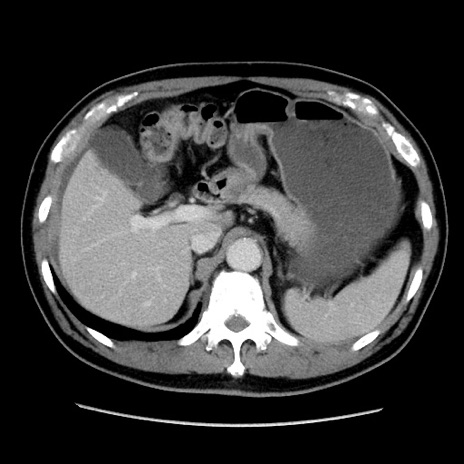

冠状断像

症例16(横断像)

【症例】 70歳代男性

【主訴】 腹痛、嘔吐

【現病歴】 約1ヶ月前より間欠的に腹痛と嘔吐あり、当院消化器内科を受診したところCTで多発する肝臓のLDAを指摘され、精査中であった。以降は消化器症状は安定していたが、2日前より嘔気と腹痛があり、同日より排便・排ガスが消失した。改善認めず、 本日、救急外来を受診した。

【既往歴】 大腸ポリープ切除後。

【身体所見】意識清明・会話良好、BT 36.3℃、BP 127/80mmHg、 P 80bpm、腹部:膨満あり、平坦・軟、上腹部正中および下腹部正中に圧痛あり、反跳痛なし、筋性防御なし。

【データ】WBC 7200、CRP 0.77